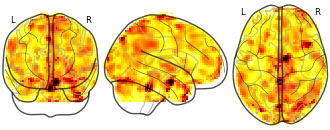

"description": "Multi-modal analysis in BPD. Brain regions exhibiting smaller gray matter and decreased activation during emotion processing in BPD compared to healthy controls. Note: Results were thresholded at p<.0025. Note2: Results were updated (see Erratum for this publication).",